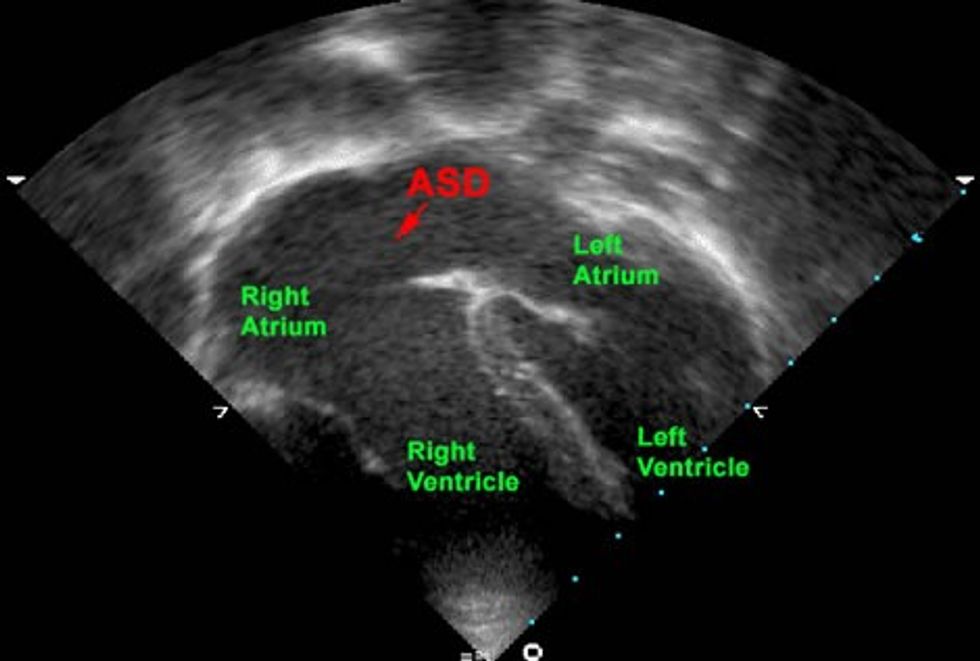

Kjo procedurë mjekësore përdoret për të mbyllur një defekt në murin që ndan dy atriumet e zemrës (defekt interatrial).

Defekti interatrial është një patologji që ndryshe njihet si “vrima në zemër” dhe përbën rreth 8% të të gjitha defekteve kongjenitale të zemrës.